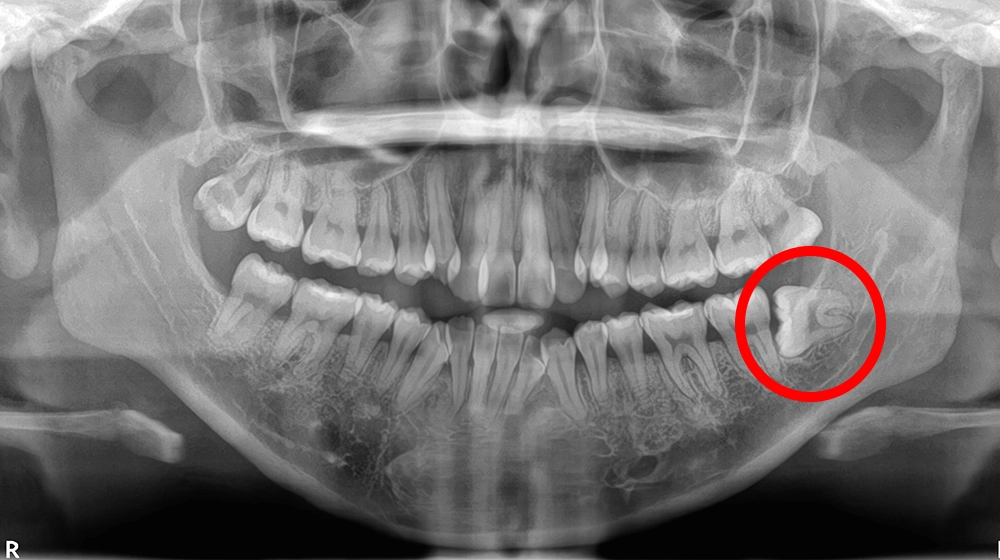

斜め/横向きに生えている

親知らず抜歯

斜め/横向きに生えている親知らずイメージ

費用(1本) 約1,500〜4,000円

抜歯時間 約5〜15分